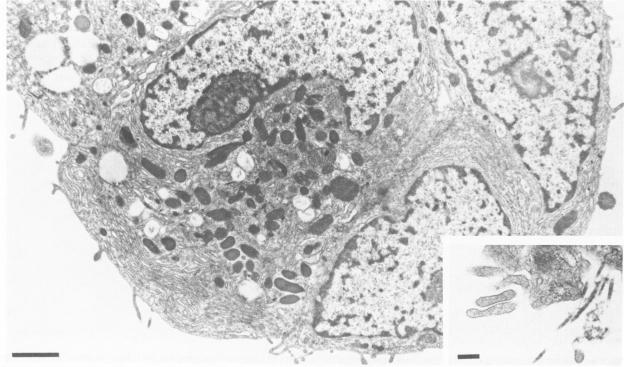

The authors have previously described a transplantable pancreatic acinar carcinoma that comprises cells which reorganize and display normal epithelial orientation only when in contact with basement membrane (BM) in vivo. In the present study, they investigated whether exogenous acellular BM or collagenous stroma (prepared from human amnion) was sufficient to reorient pancreatic acinar tumor cells in vitro. Mechanically dispersed tumor cells could not spontaneously attach to standard culture substrata; yet they adhered to exogenous intact BM or to dishes coated with purified laminin or Type IV collagen. Cell contact with amniotic BM resulted in tumor cell shape changes, assembly of intracellular actin into fibrous bundles, and restoration of normal epithelial cell-cell interactions. Computerized morphometry confirmed that tumor cells exhibited a normal polarized distribution of lipid droplets, nuclei, Golgi complexes, and zymogen granules (from base to apex) within 6 hours of culture on BM. Adhering zonules and microvilli were observed only along apical tumor cell surfaces, although full junctional complexes and distinct membrane domains did not reform. Similar attachment, cytoskeletal alterations, and reorientation occurred in the absence of protein synthesis (25 micrograms/ml cycloheximide). In contrast, tumor cells that were maintained on amniotic stroma remained round, displayed circumferential rings of actin, and appeared randomly oriented. Thus, BM may normally serve to integrate and maintain individual cells within a polarized epithelium.